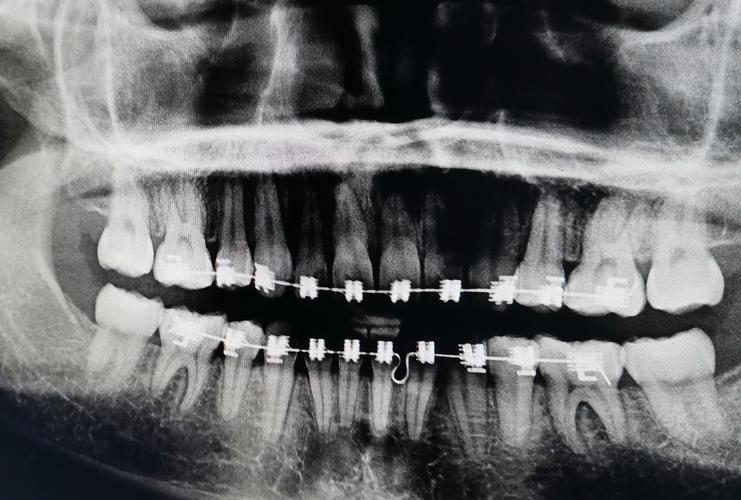

案例展示:真实见证,效果看得见

案例1:青少年骨性龅牙矫正

患者:小明,14岁,主诉“牙齿前突,不敢笑”,检查显示为轻度骨性龅牙(上颌前突,下颌后缩),伴有牙列拥挤,治疗方案:拔除4颗第一前磨牙,采用自锁托槽矫正,结合微种植体支抗内收上前牙,同时使用颌板引导下颌发育,矫正周期:2年3个月,效果:牙齿排列整齐,侧面轮廓改善明显,嘴唇自然闭合,面部协调度提升。 -